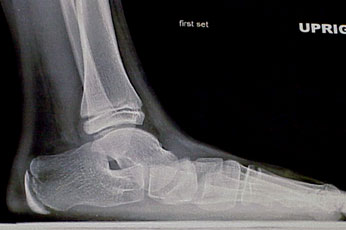

One can clinically evaluate the sagittal component by the height of the “medial arch.” It is almost impossible to assign a specific numerical measurement to this clinical observation. Evaluation of a weightbearing lateral radiograph will identify failure or “fault” along the medial column. The apex may be at the talonavicular joint, the cuneonavicular joint, the metatarsocuneiform joint or may be equally represented at all three of these locations.

Sagittal plane deformities. A line bisecting the talus on the lateral radiograph should continue distally and downward so it parallels the first metatarsal shaft. If it does this, the navicular and the first cuneiform are presumably in line as well. If it does not, then there is sagittal failure somewhere along the medial column.

This failure can occur at the talonavicular joint, the cuneonavicular joint, the first metatarsocuneiform joint or in several of these areas at the same time. This failure results in the familiar “fault.” When this occurs, the talus goes into obligatory plantarflexion and the ankle goes into some degree of equinus position. The result is a plantigrade medial side of the foot. The sagittal failure can be flexible or rigid. When it is flexible, it is referred to as forefoot supinatus. When it is rigid, it becomes irreducible forefoot varus. The effect on subtalar range of motion varies from case to case but generally requires subtalar pronation to get the medial column down to the weightbearing surface.

Standing AP radiographs show the AP talocalcaneal angle is preserved. The lateral radiograph shows marked medial column collapse.